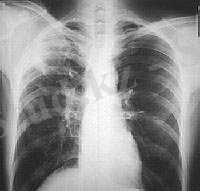

Зақымданған бауыр бірнеше есе ұлғаяды. УДЗ, рентген арқылы анықталады. Тек ота жасау арқылы емделеді.

Мидың, бүйректің, өкпенің эхинококпен зақымдануы